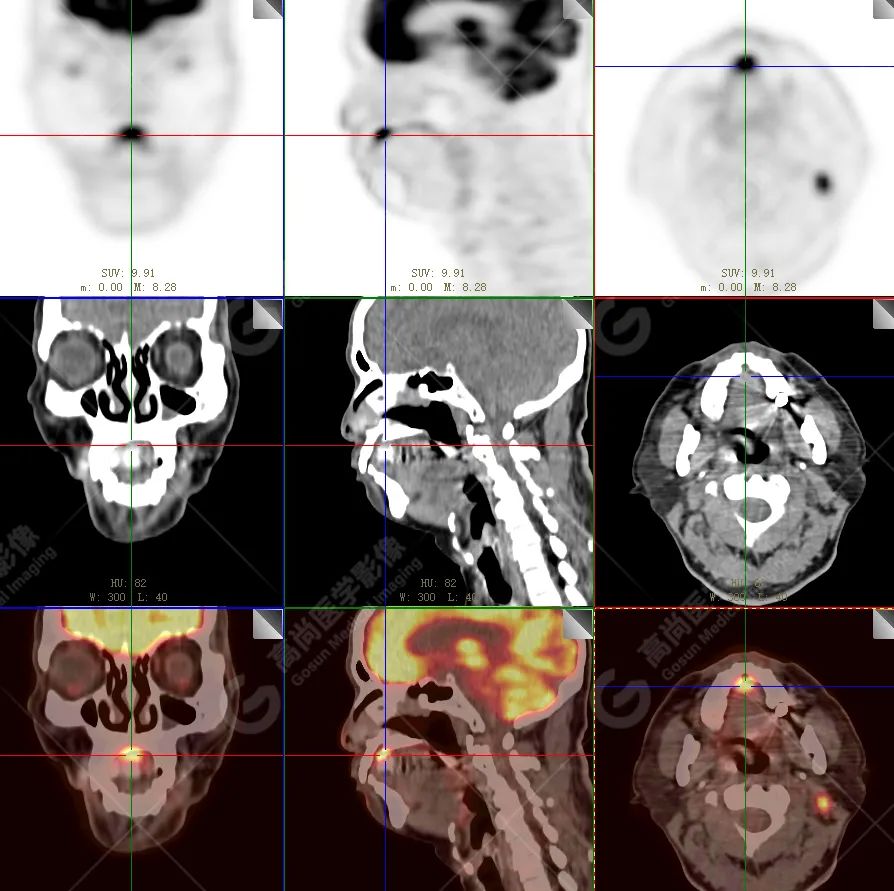

PET/CT 示:

上腭前部见一结节状放射性摄取增高影,大小约 1.6 cm×1.4 cm×1.0 cm,SUV 最大值为 10.5,CT 于上述部位见软组织密度影,边界不清,CT 值约 73 Hu(假牙金属伪影较多致 CT 值偏高)。右侧颈部(Ⅱ、Ⅲ区)及左侧颈部(Ⅰb、Ⅱ、Ⅲ区)见多发结节状及块状放射性摄取增高影,最大约 2.7 cm×2.6 cm×3.1 cm,部分放射性摄取增高,SUV 最大值为 17.7,部分病变内见放射性减低区,CT 于上述部位见增大淋巴结影。

PET/CT 结论:

1. 上腭前部结节状高代谢病灶,多考虑为恶性肿瘤(结合病史,较倾向于黑色素瘤),请结合病理学检查。

2. 右侧颈部(Ⅱ、Ⅲ区)及左侧颈部(Ⅰb、Ⅱ、Ⅲ区)多发淋巴结转移。

病理结果:

恶性黑色素瘤。